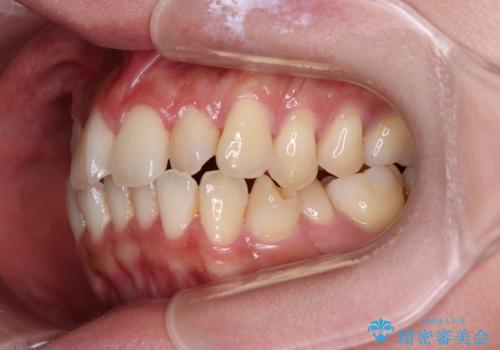

- 上下前歯のデコボコやクロスバイトを気にして来院された患者様です。

上顎歯列が下顎の歯列に対して狭小であり、一部下顎の奥歯が上顎よりも外側に位置している状態でした。

上顎の急速拡大装置を使用して上顎骨を側方に拡大することで上顎歯列を拡大し、下顎歯列も拡大できるようにすることで、歯列を整えることとしました。

歯列矯正では基本的に骨格を改善することはできませんが、急速拡大装置(MARPE)を使用することで上顎骨を側方に拡大させることができ、咬合状態を大きく改善することができます。